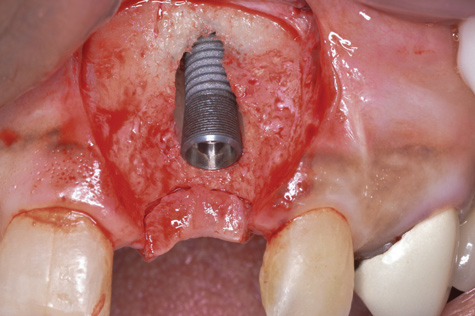

(6.) A 3.6-mm diameter implant was removed with a 4.0-mm diameter trephine drill. The apical portion of the implant was luxated carefully to preserve as much bone as possible.

Figure 6

(7.) Because apical and lateral bone volume was preserved with use of an ultrathin trephine, a wider diameter, 4.2-mm implant was placed at the time of implant removal. Bone augmentation was performed, and submerged healing was selected.

Figure 7